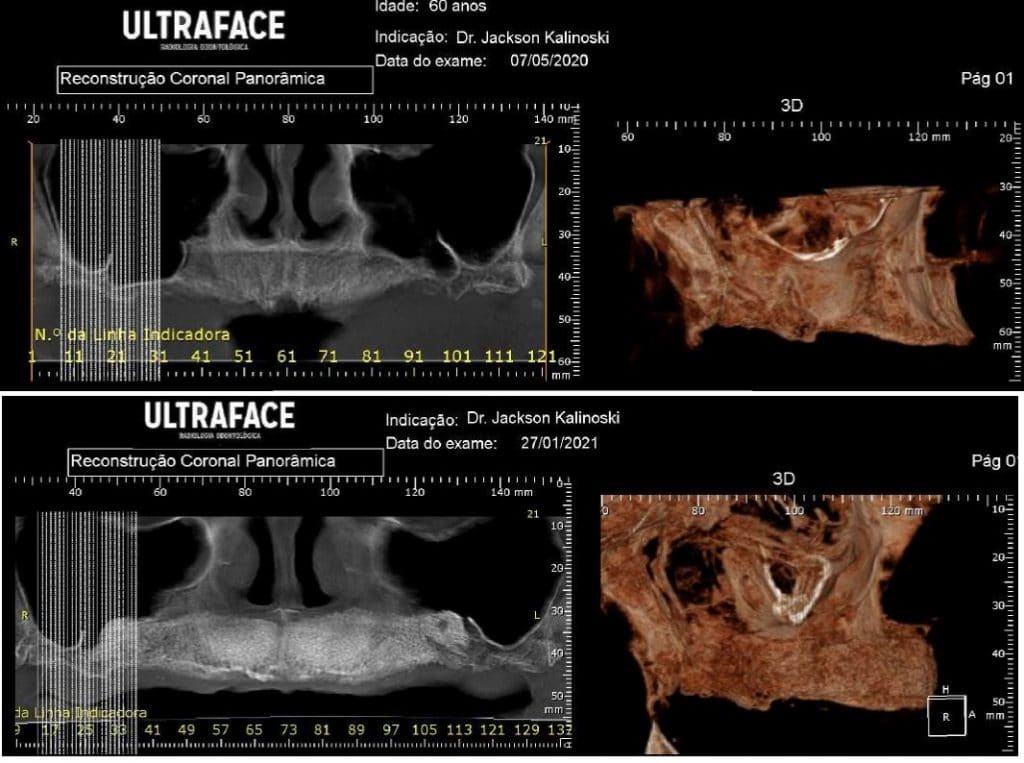

Olá colegas, aqui está um caso didático de reconstrução óssea total da maxila, levantamento do seio maxilar bilateral e bloqueio espesso com aplicação do conceito de PRF e Biotensigrity.

Após 6 meses de maturação óssea e implantes instalados com torque médio de 35 N / cm2.